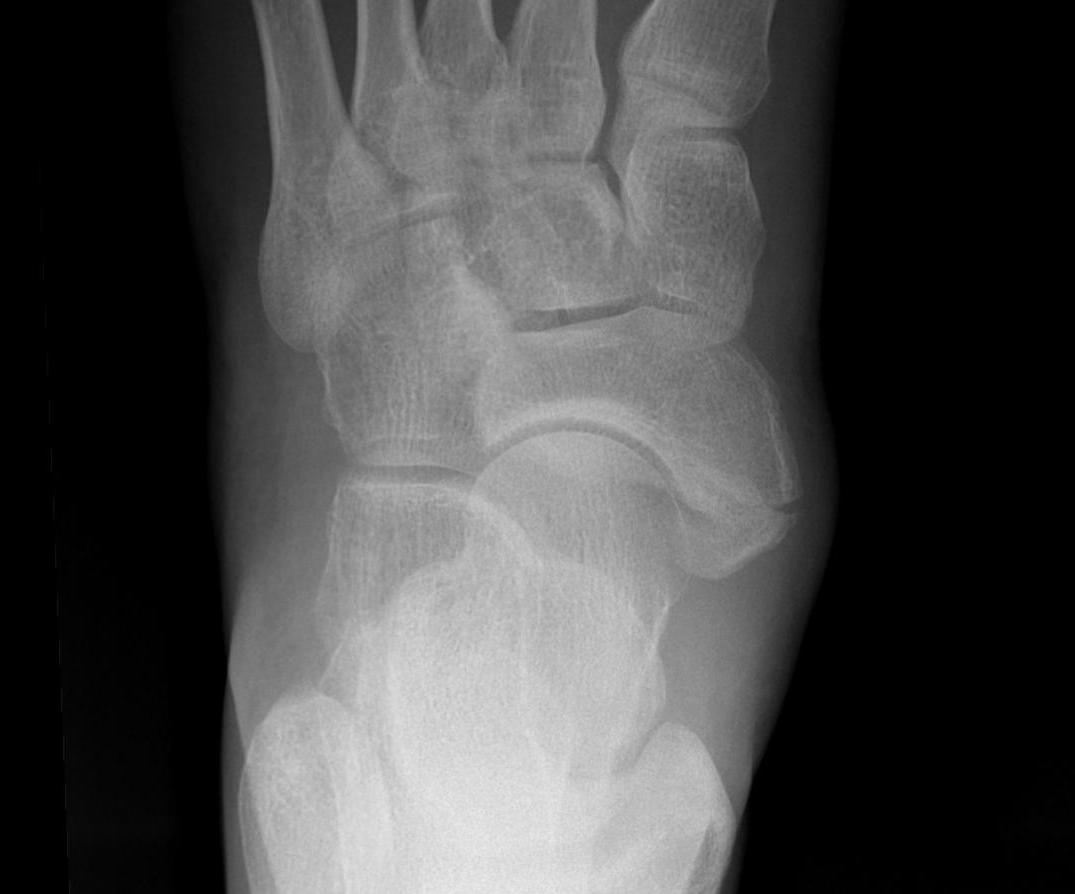

Classification

| Type I | Type II | Type III |

|---|---|---|

|

Small ossicle proximal to insertion In the Tibialis posterior tendon |

Triangular ossicle Connected to navicular via syndesmosis May fracture with injury |

Enlarged medial navicular Cornuate navicular Likely that Type II accessory navicular has fused |